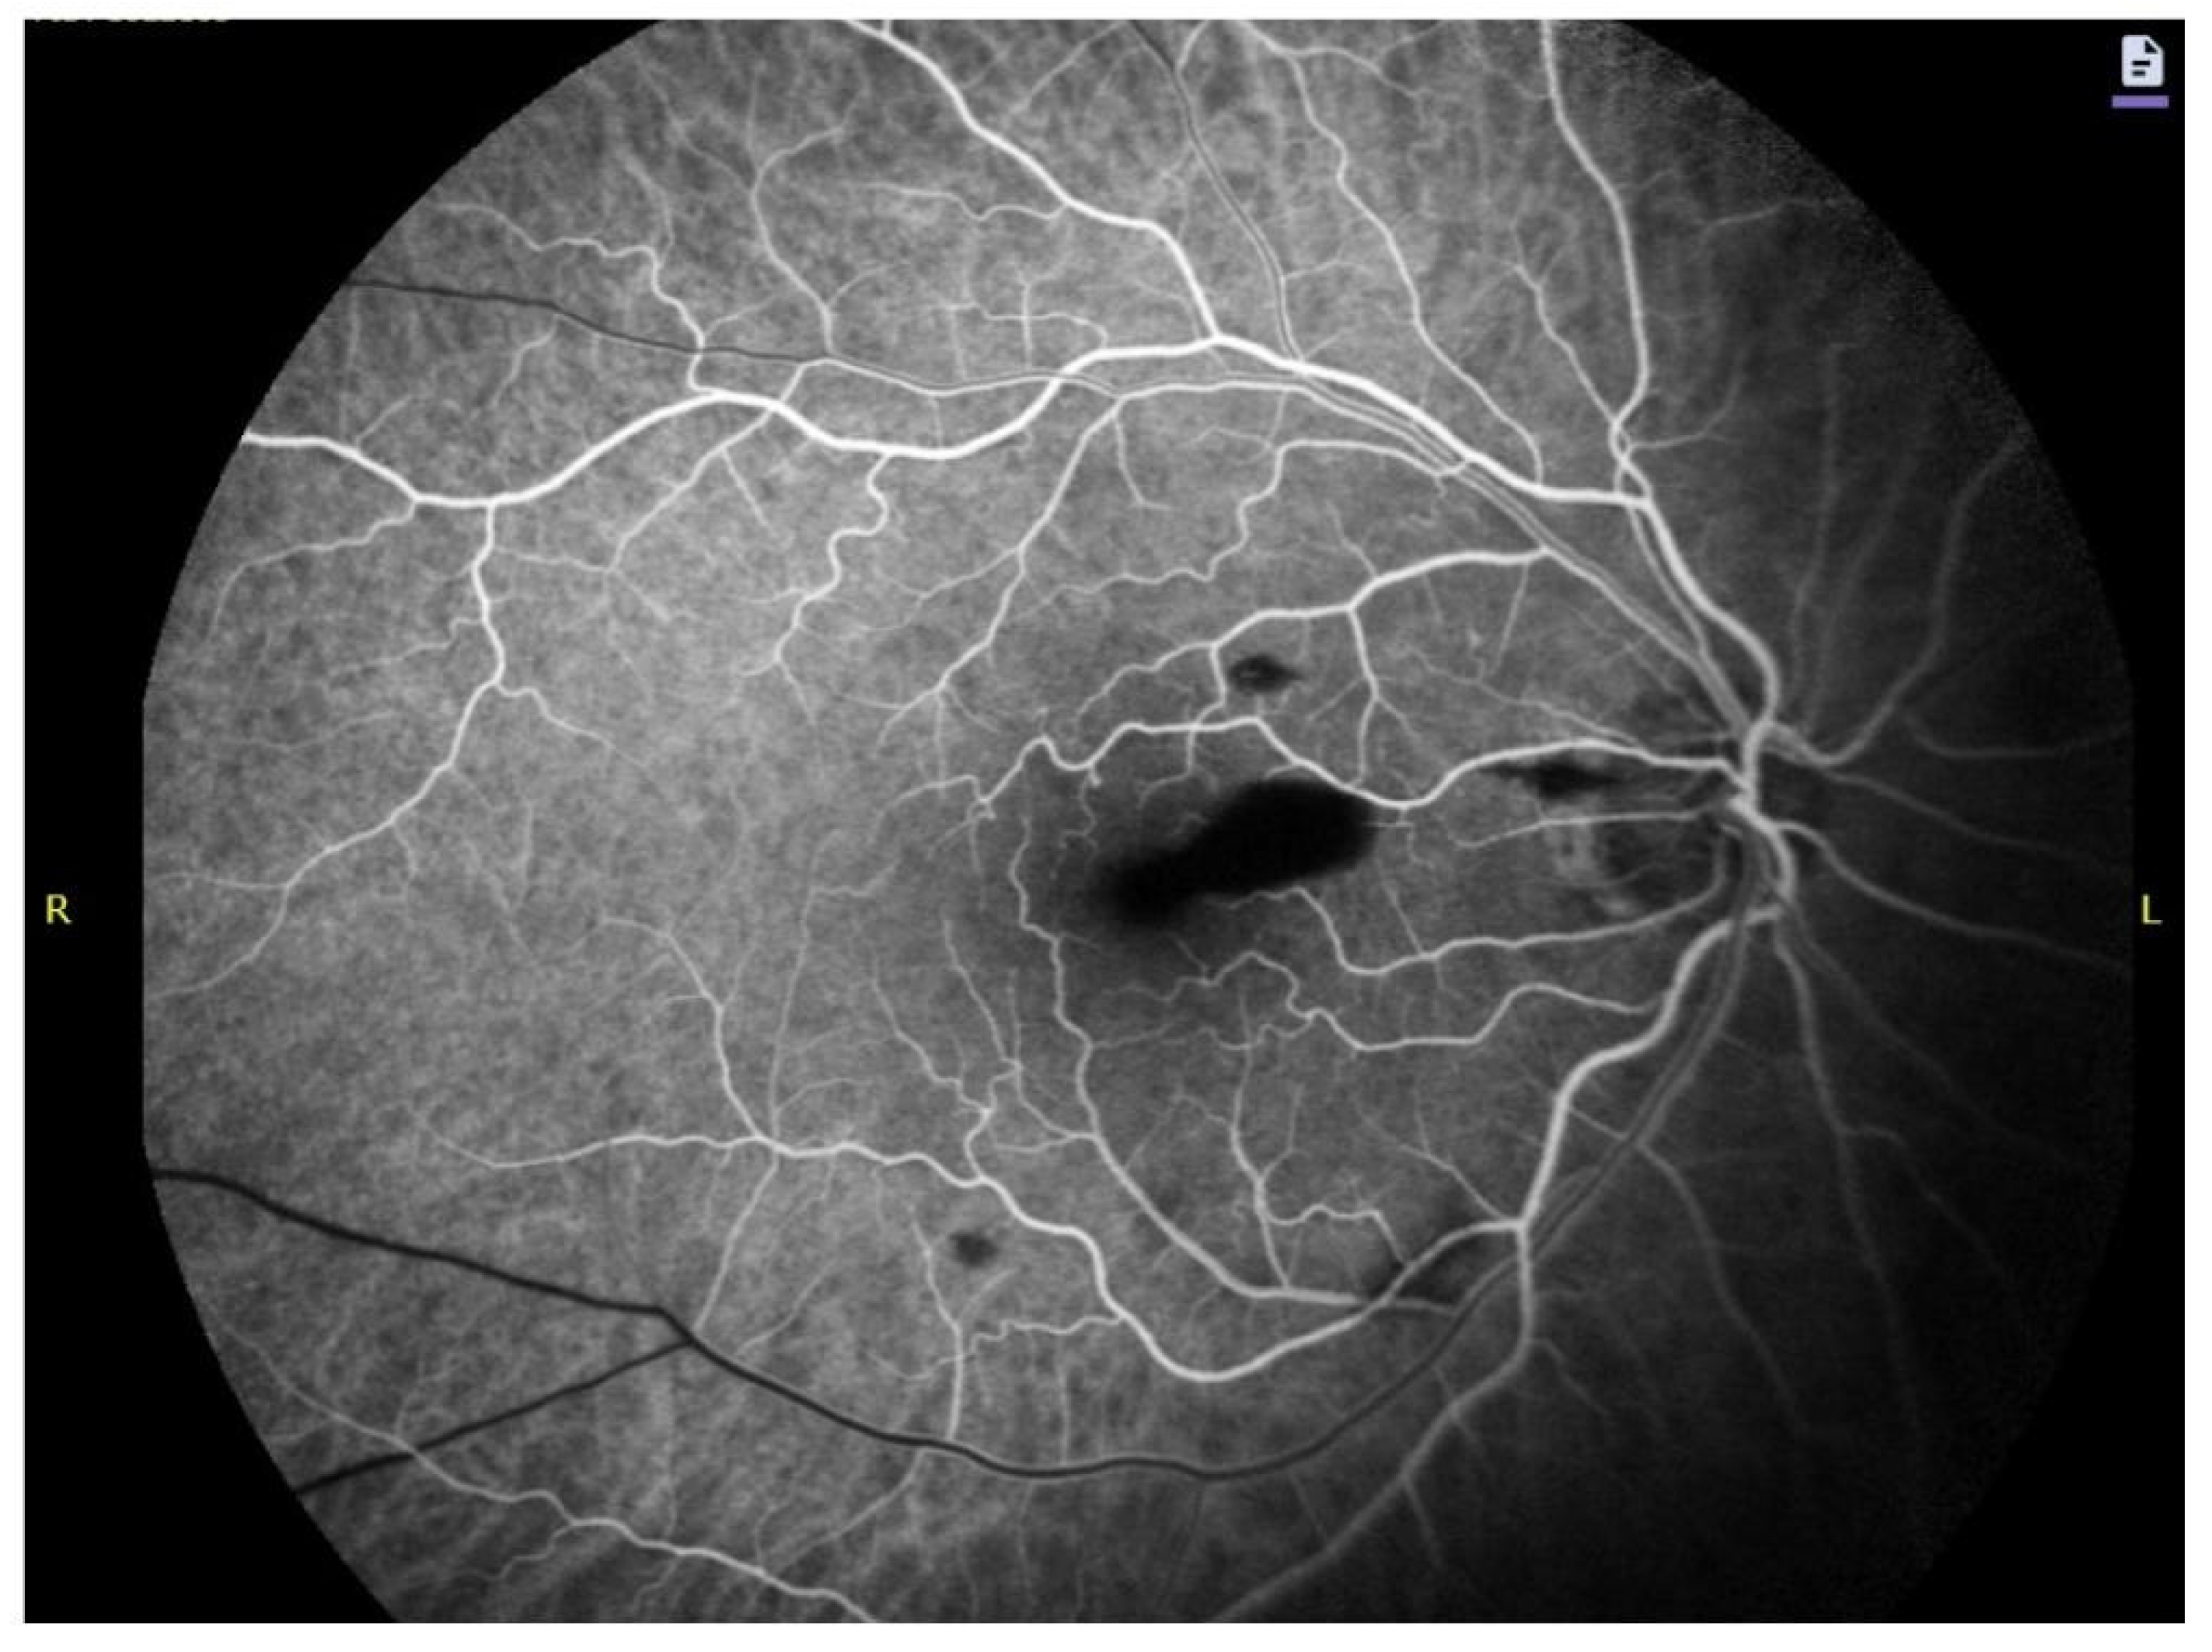

4.2. Autofluorescence, Fluorescein Angiography and Near-Infrared Signatures

4.3. Imaging Biomarkers of Hemoglobin Breakdown and Chronology